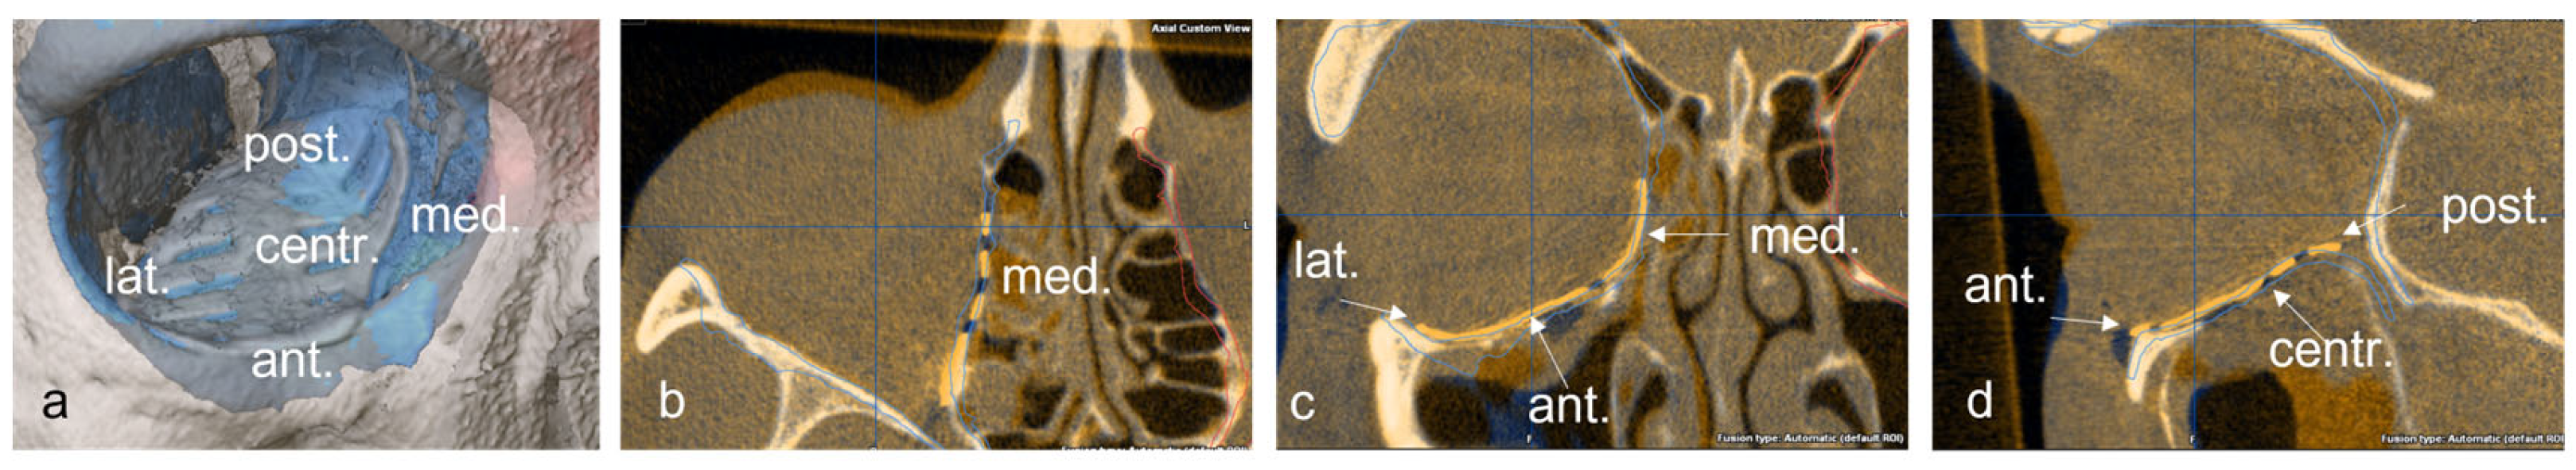

Subsequently, the position of the titanium grid in the postoperative imaging was compared with the idealized orbit. Deviations were examined and measured at the following 5 points: (1) medial implant placement, (2) lateral implant placement, (3) anterior implant placement, (4) posterior implant placement and (5) central implant placement. The software function was used for measurement, and the largest deviation in the axial, sagittal or coronal layer was drawn in the multiplanar reconstruction. The deviation at the corresponding position was determined in mm (Figure 4 and Figure 5).

Figure 4.

Representation of the five measuring points on the implant in the 3D reconstruction (a), and in the axial (b), coronal, (c) and sagittal (d) slices of the CT.